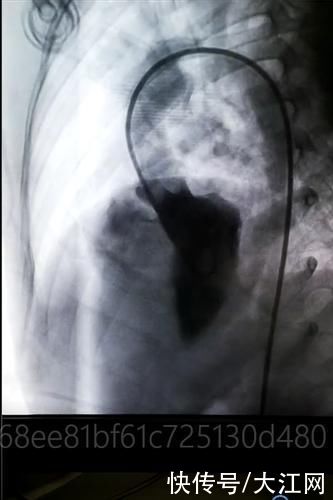

病例一:男孩(术前)

文章插图

病例一:男孩(术后)